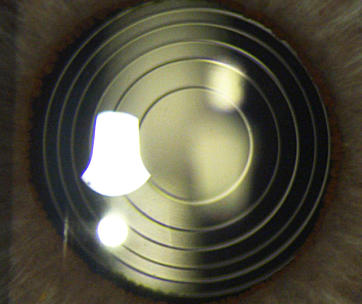

Bei Wunsch nach bestmöglicher Unabhängigkeit von Sehbehelfen ab dem 45. Lebensjahr ist der operative Austausch der eigenen Augenlinse durch eine multifokale Intraokularlinse die optimale Methode. Diese Kunststoffimplantate sind vergleichbar zu den jedes Jahr weltweit millionenfach eingebauten Kunstlinsen im Rahmen einer klassischen Katarakt-OP, sie haben im Gegensatz zu den dabei verwendeten „einfachen“ Einstärkenlinsen einen hochspezialisierten Schliff. Dieser bewirkt, dass neben einem sehr guten Fernblick auch scharfes Sehen im Arbeitsbereich und in der Nähe erreichbar wird, und trotzem das räumliche Sehen ungestört bleibt. Ebenfalls zu den Premiumlinsen gehören die torischen Intraokularlinsen, die neben einer Weit-, oder Kurzsichtigkeit gleichzeitig auch eine Hornhautverkrümmung (Astigmatismus) mitkorrigieren können.

Bei Wunsch nach bestmöglicher Unabhängigkeit von Sehbehelfen ab dem 45. Lebensjahr ist der operative Austausch der eigenen Augenlinse durch eine multifokale Intraokularlinse die optimale Methode. Diese Kunststoffimplantate sind vergleichbar zu den jedes Jahr weltweit millionenfach eingebauten Kunstlinsen im Rahmen einer klassischen Katarakt-OP, sie haben im Gegensatz zu den dabei verwendeten „einfachen“ Ein stär - ken linsen einen hochspeziali - sierten Schliff. Dieser bewirkt, dass neben einem sehr guten Fernblick auch scharfes Sehen im Arbeitsbereich und in der Nähe erreichbar wird, und trotzem das räumliche Sehen ungestört bleibt. Ebenfalls zu den Premiumlinsen gehören die torischen Intraokular - linsen, die neben einer Weit-, oder Kurz - sichtigkeit gleichzeitig auch eine Hornhaut - verkrümmung (Astigmatismus) mitkorri - gieren können.

Premiumlinse die besseren Implantate? Der viel strapazierte Begriff der Premium - linse ist unglücklich gewählt, geeigneter wäre das Wort Speziallinse “. Solche Implantate sind nämlich nicht „bessere“ Linsen als die bei der klassischen Katarakt- OP implan tierten Einstärkenlinsen, sie haben lediglich erweiterte Eigen schaf ten , gleich zeitig aber auch unerwünschte Begleitphänomene wie ein vermin der tes Kon trast sehen , eine erhöhte Blend - empfind lichkeit , ein schlech teres Dämmerungs sehen und oft auch eine minimale Unschärfe in der Ferne . Ein gesundes Auge, ein gutes optisches System und die Anpassungsfähigkeit unseres Gehirns („ neuronale Adaptation “) kompen sieren diese meist nur anfänglich bemerkten Begleitphänomene.

Sehen lernen mit Multifokallinsen - Neuronale Adaptation - Alle multifokalen Linsen wirken über einen optischen Trick, der mehrere Schärfepunkte auf der Netzhaut erzeugt. Echte Akkommodation (Scharfstellen der Dioptrien in der Nähe durch Dickenänderung der Linse) wie im jugendlichen Alter ist bis heute mit Kunstlinsen leider nicht zufriedenstellend gelungen. Deshalb brauchen multifokale Linsen einen besonderen Schliff zur Bilderzeugung, um dieses Defizit wett zu machen. Die auf der Netzhaut übereinander projizierten Bilder müssen vom Patienten erst als solche „entdeckt und herausgefiltert“ werden. Das bedeutet, dass mit einer Multifokallinse das neue Sehen „gelernt“ werden muss, was in fast allen Fällen nach Abnahme des Verbandes schon nach wenigen Minuten gelingt. Unser Gehirn vermag diesen neuen Seheindruck rasch und gut zu verwerten und die gleichzeitig unerwünschten Phänomene auszublenden. Diese besondere Leistung wird als „neuronale Adaptation“ bezeichnet und ist ein entscheidender Faktor für die hohe Zufriedenheit mit solchen Spezialimplantaten.